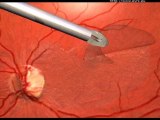

In the case of a cataract, the crystalline lens loses its transparency. The crystalline lens is this small lens behind the pupil that converges the photons on the retina, and that enables the eye to focus. If the crystalline lens becomes uniformly opaque, it will let fewer photons pass through, and vision will progressively blur, with possible alteration of color vision.